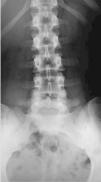

En la analítica de sangre había presencia de un factor HLAB27 positivo, pero las otras pruebas reumáticas dieron negativas. Los exámenes de imágenes, radiografías e IRM eran normales (figs. 1-5).

Figura 1. Radiografía de frente en AP del raquis lumbar. Además de una ligera escoliosis lumbar de convexidad izquierda, probablamente en relación con el acortamiento del miembro inferior izquierdo, el cliché era normal.